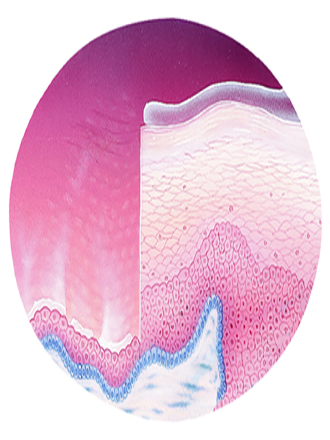

The image represents changes in the vaginal epithelium with menopause. The reproductive years are shown on the right and menopause on the left.

Demonstrates thinning of the top layer of superficial epithelial cells; decrease in collagen affects elasticity and thickness. Because of this patient may experience vaginal dryness, burning, pruritus, discharge, bleeding, and dyspareunia.